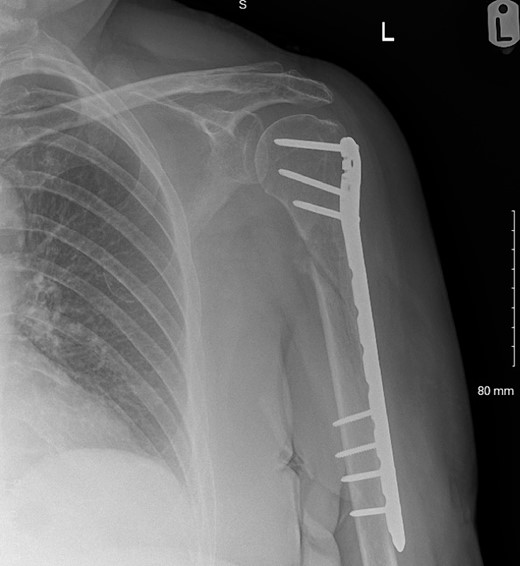

The fracture was neurologically intact at presentation to the local service but at 3 months follow-up, painful hypertrophic non-union was evident so open reduction and internal fixation [with a De Puy Synthes proximal humeral internal locking system (PHILOS®) and two Arthrex FiberTape® Cerclages; Fig. 1] was performed. Immediately post-operatively, the patient had MRC 0/5 power in brachioradialis, extensor carpi radialis longus, extensor digitorum communis, extensor pollicis longus, and extensor indicis proprius with spontaneous paresthesia and anesthesia in the superficial radial nerve cutaneous distribution.